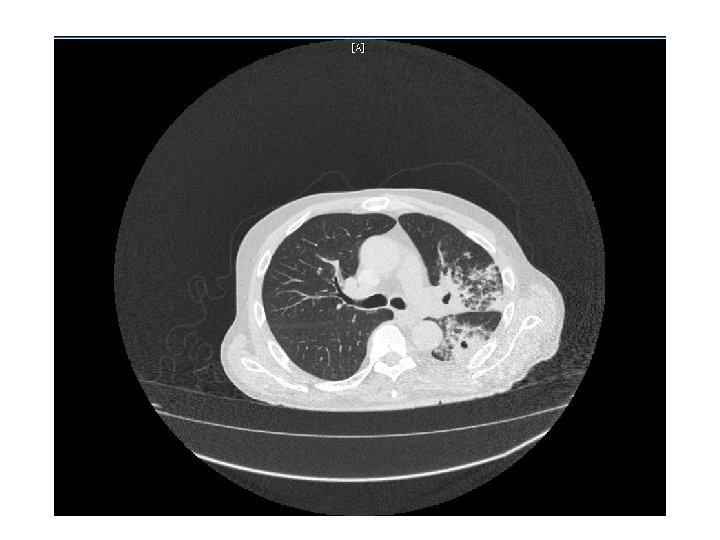

CT Chest • Multiple cavitary lesions • Largest left lung apex 3. 8 x 4. 7 cm with nodular thickened wall • Smaller cavitary lesions in L lung base • R lung: smaller areas of ground-glass opacities with areas of tree in bud appearance.

Chest radiography • Active disease: upper lobe infiltration/ cavity/ effusion • Healed: nodules, fibrotic scars, calcified granulomas or basal pleural effusion • Normal in latent TB • HIV: infiltrate in any lung zone, mediastinal or hilar LAD, normal